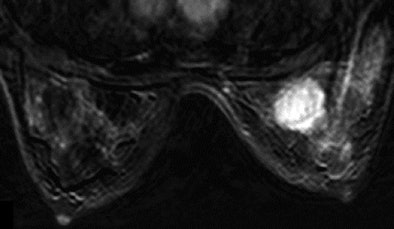

| Above, subtracted contrast-enhanced T1-weighted axial MR image shows focal area of intense F-18 FDG uptake and marked gadolinium enhancement in superior inner quadrant of right breast. |